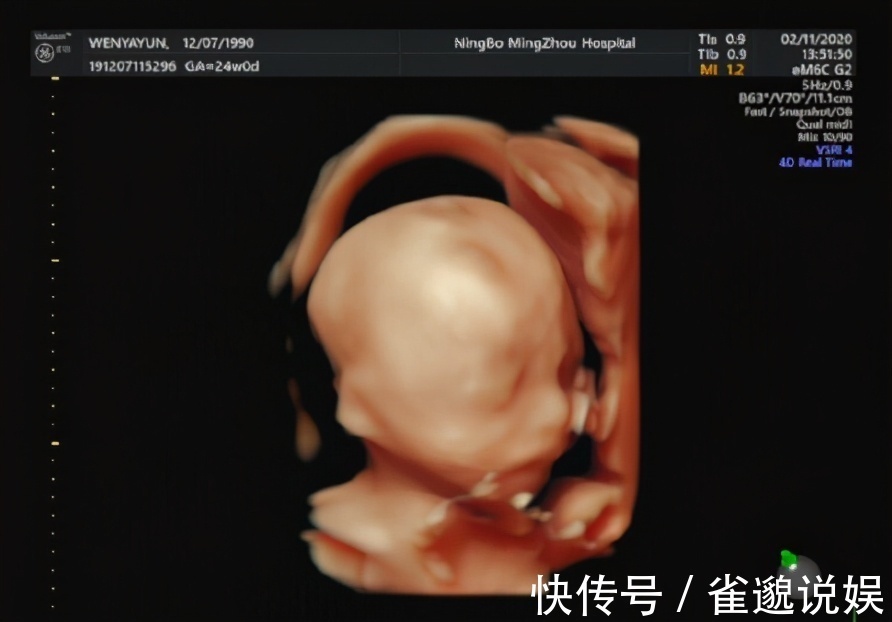

? 做排畸B超,孕妈需要提前了解几点:① 普通B超(三维)也完全可以起到排畸的效果,只是四维B超可以算是宝宝的第一张照片,比较有意义;② 就算排畸B超顺利通过,胎儿出生后也还可能存在畸形,毕竟B超也不是万能的,这些准爸妈要正确认识;③ 检查时孕妈要心态平和,避免过分紧张,不然会影响胎宝宝的面部表情成像;如果检查一次没看清楚,医生建议复查,也不要太紧张,配合医生检查就好,一般都能顺利通过。